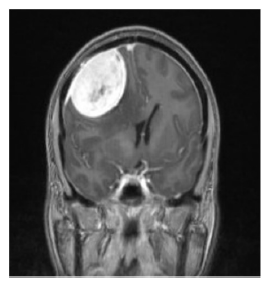

Glioblastoma Multiforme

Grade 4 Astrocytoma

• Most aggressive tumor form (grows in 1-2 months)

• Average survival rate from diagnosis approx. 2 years

• Higher Incidence in white individuals